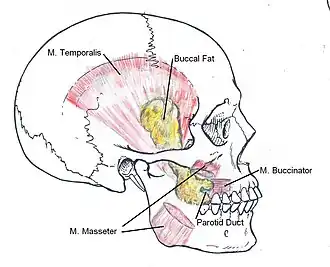

The buccal fat pad (also called Bichat’s fat pad, after Xavier Bichat, and the buccal pad of fat) is one of several encapsulated fat masses in the cheek. It is a deep fat pad located on either side of the face between the buccinator muscle and several more superficial muscles (including the masseter, the zygomaticus major, and the zygomaticus minor).[1] The inferior portion of the buccal fat pad is contained within the buccal space. It should not be confused with the malar fat pad, which is directly below the skin of the cheek.[2] It should also not be confused with jowl fat pads. It is implicated in the formation of hollow cheeks and the nasolabial fold, but not in the formation of jowls.[3]

The buccal fat pad is composed of several parts, although exactly how many parts seems to be a point of disagreement and no single consistent nomenclature of these parts has been observed. It was described as being divided into three lobes, the anterior, intermediate, and posterior, “according to the structure of the lobar envelopes, the formation of ligaments, and the source of the nutritional vessels”.[1] Also, there are four extensions from the body of the buccal fat pad: the sublevator, the melolabial, the buccal, and the pterygoid. The nomenclature of these extensions derives from their location and proximal muscles.[4]

The anterior lobe of the buccal fat surrounds the parotid duct, which conveys saliva from the parotid gland to the mouth. It is a triangular mass with one vertex at the buccinators, one at the levator labii superioris alaeque nasi, and one at the orbicularis oris. The intermediate lobe lies between the anterior and posterior lobes over the maxilla.[1][4] The intermediate lobe seems to lose a significant amount of volume between childhood and adulthood. The posterior lobe of the buccal fat pad runs from the infraorbital fissure and temporal muscle to the upper rim of the mandible and back to the mandibular ramus.